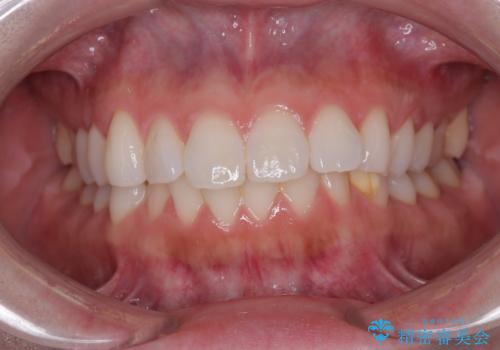

- 上下前歯の叢生を気にして来院された患者様です。

軽度な叢生であり、安価で短期間の治療を規模されていたため、インビザライン・モデレートを用いて矯正治療を行うこととしました。